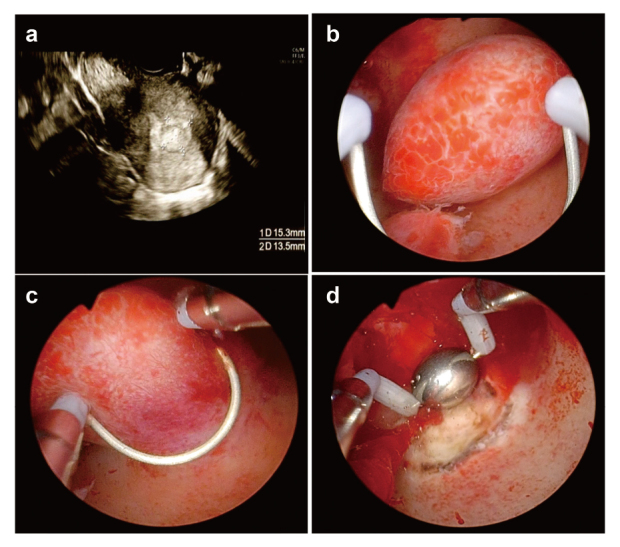

Von Willebrand disease (VWD) is a bleeding disorder caused by a congenital quantitative reduction, deficiency, or qualitative abnormality of the von Willebrand factor (VWF). Here, we report a case of delayed postoperative bleeding in an infertile woman with endometrial polyps complicated by VWD. The patient was a 39-year-old infertile woman with type 2A VWD. At 38 years of age, she was referred to our hospital for infertility and heavy menstrual bleeding. Hysteroscopy revealed a 15-mm polyp lesion in the uterus. The patient was scheduled for transcervical resection (TCR) of the endometrial polyp. Gonadotropin-releasing hormone agonists were preoperatively administered to prevent menstruation. The VWF-containing concentrate was administered for 3 days according to guidelines. The patient was discharged on postoperative day 3 after confirming the absence of uterine bleeding. Uterine bleeding began on postoperative day 6. The patient was readmitted on postoperative day 7 and treated with VWF-containing concentrate for 5 days, after which hemostasis was confirmed. TCR surgery for endometrial lesions is classified as a minor surgery, and guidelines recommend short-term VWF-containing concentrate replacement. However, it should be kept in mind that only short-term VWF-containing concentrate replacement may cause rebleeding postoperatively.